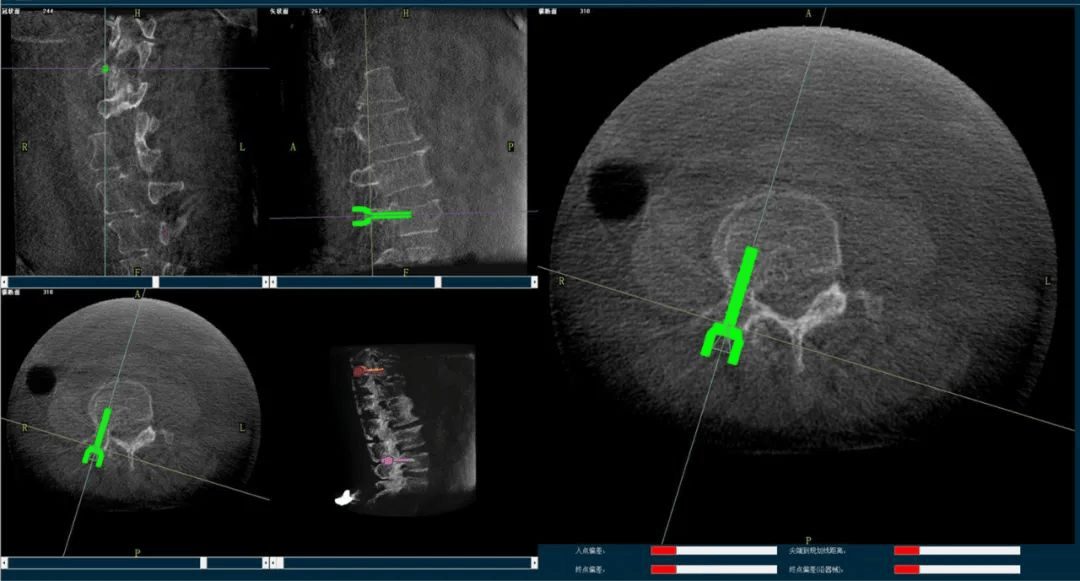

骨科导航机器人规划图像

术中,手术团队先对患者进行三维影像扫描,将图像同步传输至机器人成像系统后,利用骨科导航机器人系统做好手术规划,随后利用其机械臂,将手术工具精确定位到“目的地”,铺好“通道”,这就很好的解决了医生“盲穿”的问题。

主任为患者注射骨水泥,再次影像扫描后,发现骨水泥进入位置非常好,弥散效果更佳,手术顺利完成,患者的恢复也自然更好。